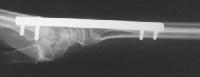

Clinical Example: Distraction plate fixation distal radius fracture

distal radius fracture